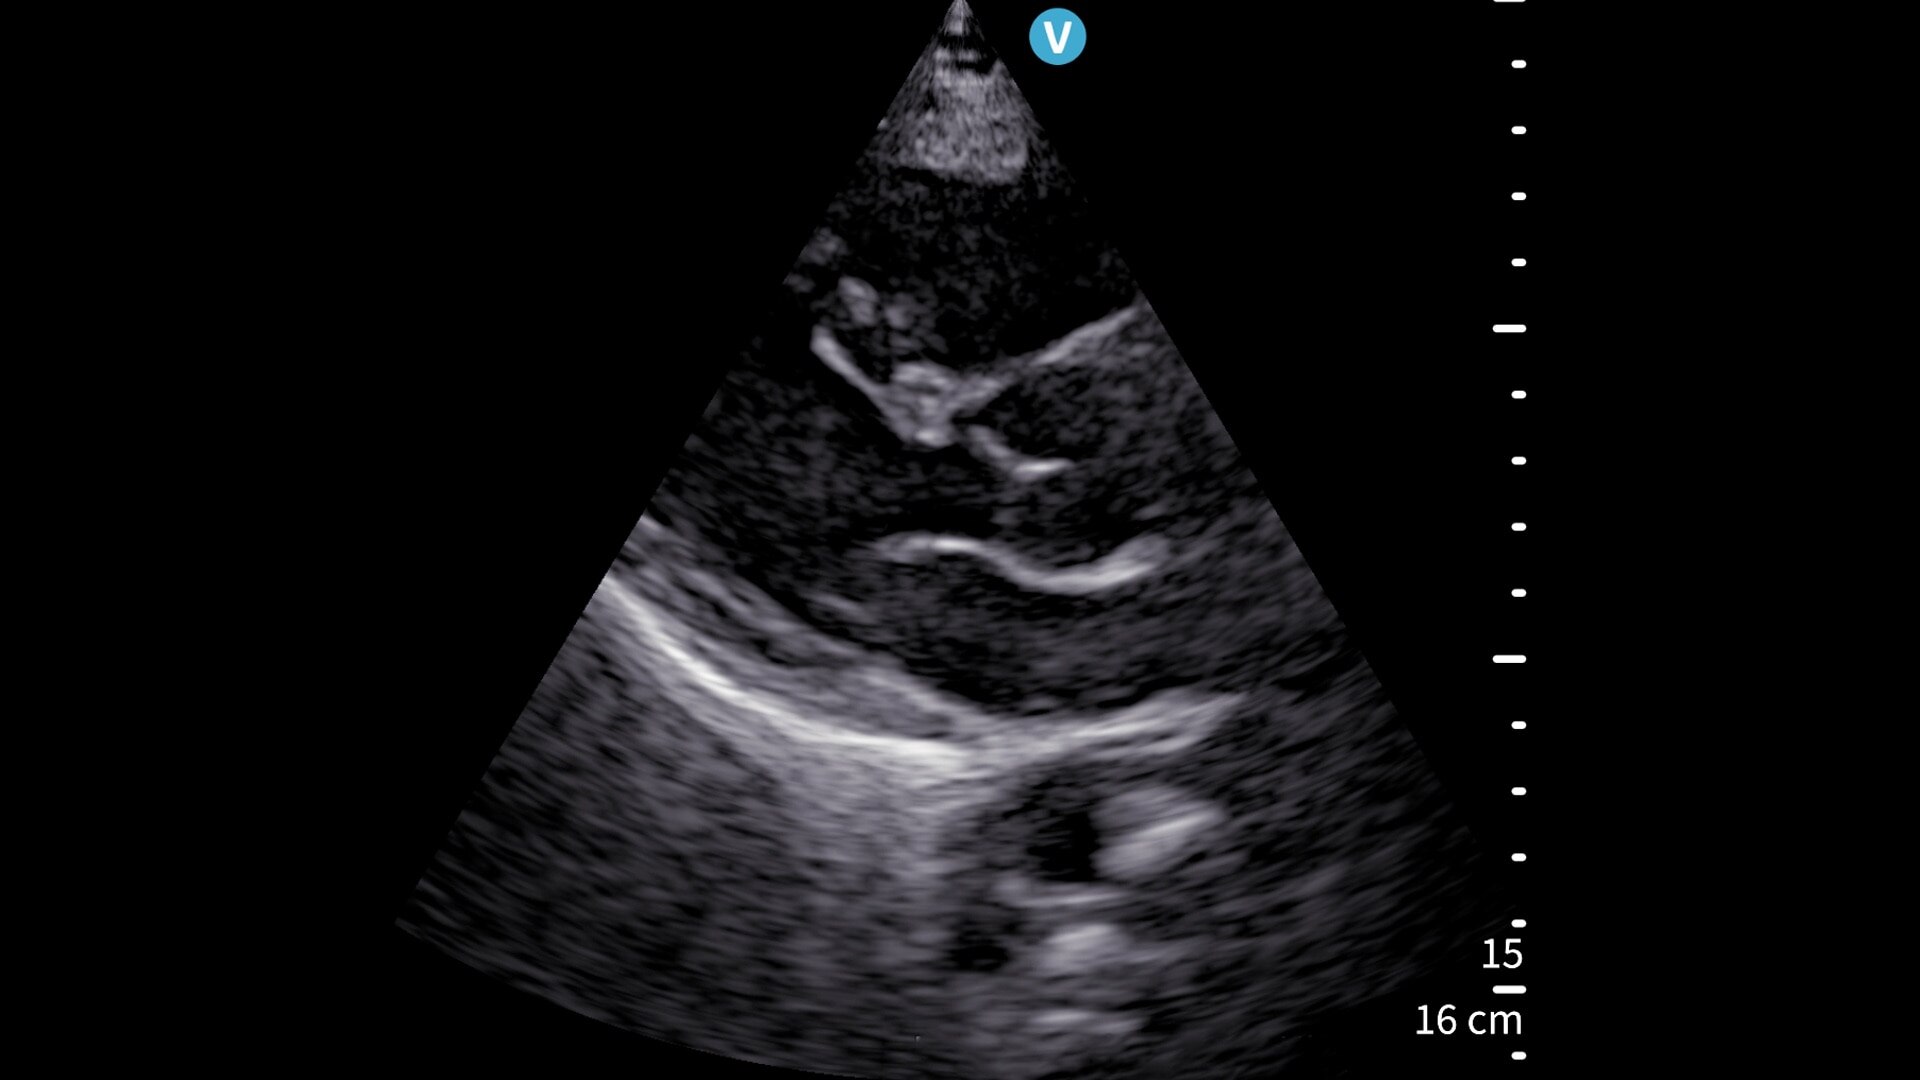

Vscan Air SL offers sector and linear transducers in a dual-probe configuration. Its sector transducer is ideal for rapid cardiac assessments. The opposite side of the probe has a linear array, so you won’t miss a beat when moving from a cardiac to a vascular assessment.

Sector array: Abdominal (Adult/Pediatrics), Urology (Adult/Pediatrics), OB/GYN, Lung/Thoracic (Adult/Pediatrics), Cardiac and hemodynamic assessment, Adult cephalic/Transcranial doppler, procedure guidance (Adult/Pediatrics).